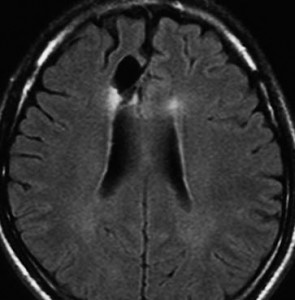

フレア画像です。左上前頭回の星細胞腫ですが,境界がとてもはっきりしていて限局性 localized single gyrus glioma です。びまん性 diffuseには見えません。IDH1の変異があり,1p/19qの欠失はないので星細胞腫グレード2です。上の例とは全く違う臨床像を示しますが,分子病理でも区別はつきません。頑張って早めに全摘出して治してしまった方がいいタイプです。再発を避けるために,supratotal resectionと言って,周囲の正常脳組織も10mmくらい余分に摘出します。